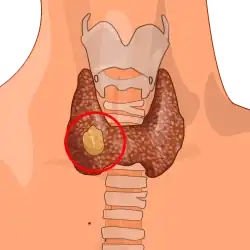

Thyroid cancer is cancer that develops from the tissues of the thyroid gland.[1] It is a disease in which cells grow abnormally and have the potential to spread to other parts of the body.[8][9] Symptoms can include swelling or a lump in the neck, difficulty swallowing or voice changes including hoarseness, or a feeling of something being in the throat due to mass effect from the tumor. However, most cases are asymptomatic.[1][10] Cancer can also occur in the thyroid after spread from other locations, in which case it is not classified as thyroid cancer.[4]

Risk factors include radiation exposure at a young age, having an enlarged thyroid, family history and obesity.[1][2][3] The four main types are papillary thyroid cancer, follicular thyroid cancer, medullary thyroid cancer, and anaplastic thyroid cancer.[4] Diagnosis is often based on ultrasound and fine needle aspiration.[1] Screening people without symptoms and at normal risk for the disease is not recommended.[10][11]

Treatment options may include surgery, radiation therapy including radioactive iodine, chemotherapy, thyroid hormone, targeted therapy, and watchful waiting.[1] Surgery may involve removing part or all of the thyroid.[4] Five-year survival rates are 98% in the United States.[5]

Globally as of 2015, 3.2 million people have thyroid cancer.[6] In 2012, 298,000 new cases occurred.[12] It most commonly is diagnosed between the ages of 35 and 65.[5] Women are affected more often than men.[5] Those of Asian descent are more commonly affected;[4] with a higher rate of mortality among Filipino females.[13] Rates have increased in the last few decades, which is believed to be due to better detection.[12] In 2015, it resulted in 31,900 deaths.[7]